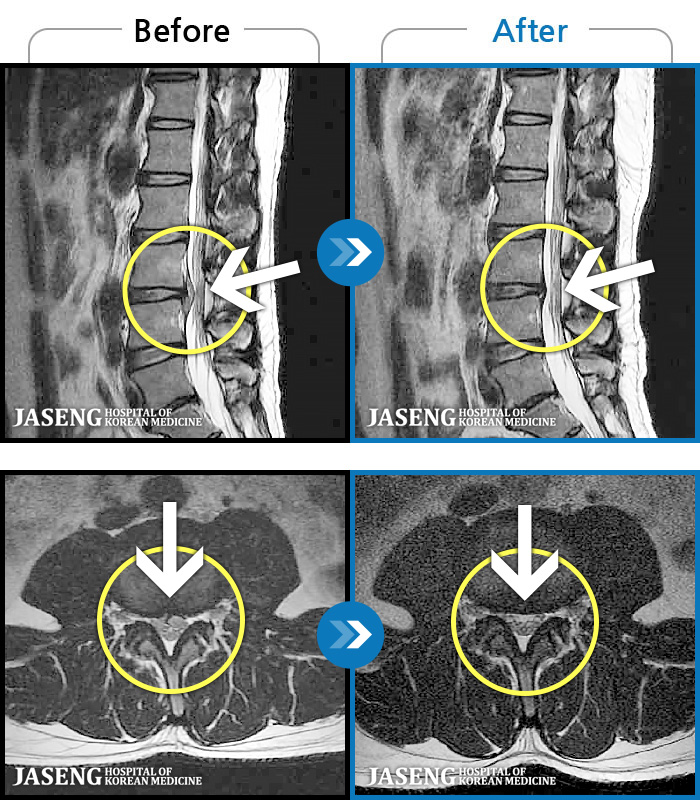

ȯںп Ǹ ǿ ԿǾ, ο ġ ۿ Ƿ ġḦ Ͻñ ٶϴ.